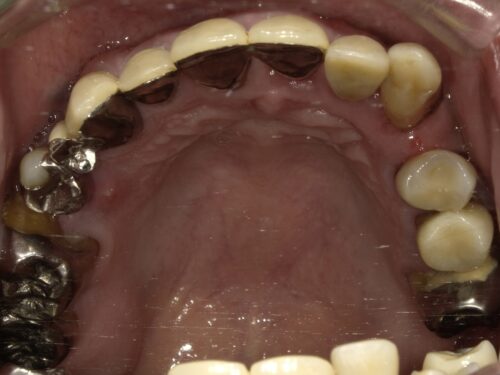

奥歯も残っていますが歯周病で根元まで見えてしまっていたり、

歯の向きが変わってしまっているところもあります。

下の大臼歯とよばれる奥歯はもうありませんでした。

歯周病の原因となる歯石(歯周病菌のかたまり)をとるために全体的にクリーニングを進めながら、

奥歯でしっかり噛めるように歯を作り、前歯の見た目も改善していきました。